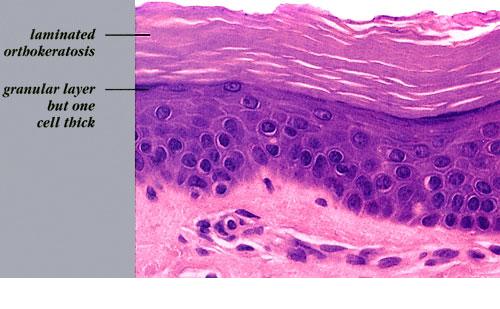

Histopathology.

The characteristic finding is the association of a moderate degree of hyperkeratosis with a thin or absent granular layer . The hyperkeratosis often extends into the hair follicles, resulting in large keratotic follicular plugs. The dermis is normal.

Labeling with tritiated thymidine shows a normal rate of epidermal proliferation . The hyperkeratosis is regarded as a retention keratosis resulting from increased adhesiveness of the stratum corneum. The reason for this, as seen by electron microscopy, is a delay in the dissolution of the desmosomal disks in the homy layer. Keratohyaline granules are regularly seen on electron microscopy, in contrast to light microscopy. The stratum granulosum, however, consists of only a single layer, and the keratohyaline granules appear small and crumbly or spongy, which is evidence of defective synthesis. The reason for the inadequate formation of keratohyaline granules lies in a defect in the synthesis of filaggrin, a histidine-rich protein . Defective profilaggrin expression in ichthyosis vulgaris may be a result of selectively impaired posttranscriptional control . In noninherited ichthyosis vulgaris associated with neoplasia, the keratohyaline granules have been described as being small but showing a normal structure, indicating a reduced but not an abnormal synthesis